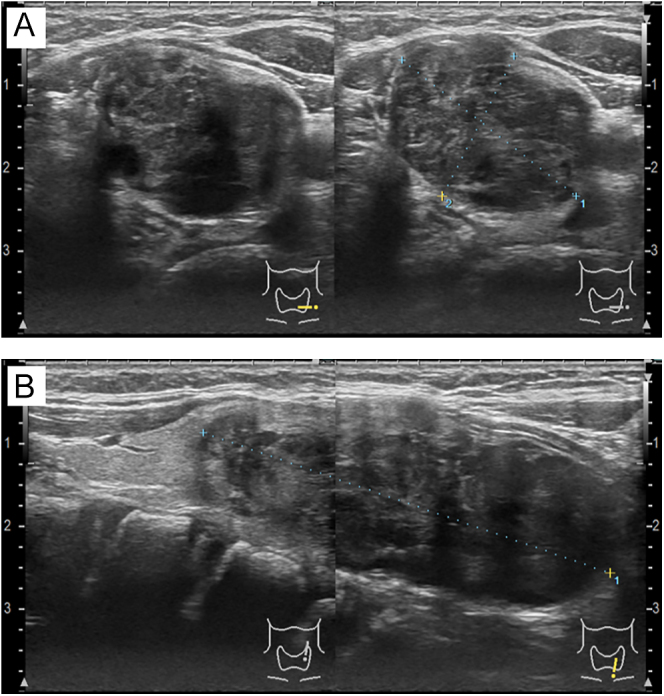

Summary: Spindle epithelial tumor with thymic-like elements (SETTLE) is an extremely rare tumor that occurs primarily in the thyroid gland. Histologically, SETTLE is characterized by the presence of spindle-shaped epithelial cells and glandular structures. However, it is known that diagnosis via fine-needle aspiration cytology can be challenging. SETTLE predominantly occurs in younger individuals and has a less favorable prognosis compared to differentiated thyroid carcinoma. Therefore, ensuring accurate diagnosis and appropriate treatment is crucial. We encountered a case of spindle epithelial tumor with thymus-like differentiation in a 10-year-old patient for whom the preoperative diagnosis was successfully established through fine-needle aspiration cytology, which facilitated appropriate surgical resection. Comprehensive histopathological examination and immunohistochemical analysis are essential to ensure appropriate management and surveillance of SETTLE.

Learning points: A rare thyroid tumor, spindle epithelial tumor with thymic-like elements (SETTLE), was diagnosed preoperatively and treated surgically. SETTLE presents with characteristic histological features that must be recognized for accurate diagnosis. In addition, diagnosis through cytology is often challenging. The primary treatment for SETTLE is surgical intervention as radiotherapy and pharmacological treatments are generally not expected to be highly effective. Radical resection is the only effective treatment, making the selection of the surgical procedure according to the stage of the disease essential.